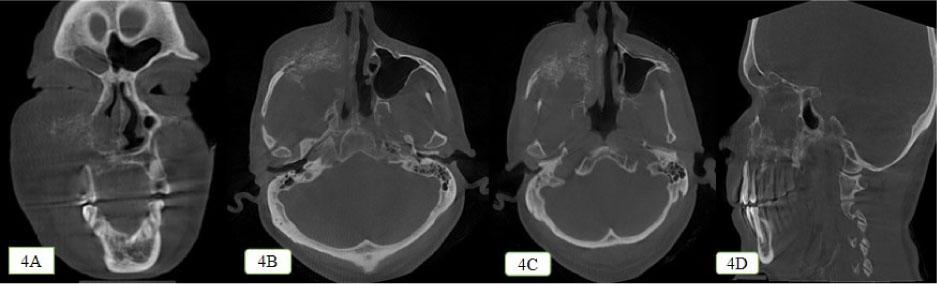

Figure 4: